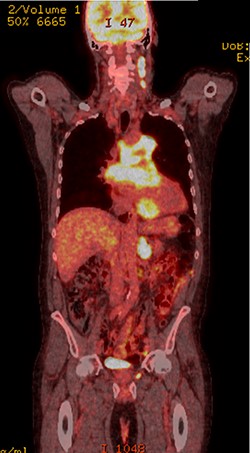

Further staging imaging was recommended by the radiology team. A CT head scan demonstrated no abnormalities, whereas CT chest–abdomen–pelvis (CAP) found significantly enlarged necrotic mediastinal lymph nodes with invasion into the pericardium and heart; bilateral adrenal nodules (suspicious for metastases) and appearances consistent with a lymphoproliferative disorder. The testicular biopsy found large lymphocytes with abundant cytoplasm and prominent nucleoli consistent with a diffuse large B-cell lymphoma (DLBCL). A positron emission tomography (PET) scan was organized at the request of the oncology team (Figs 4 and 5).

PET scan (coronal plane) showing intensely metabolically active lymphadenopathy on both sides with extra-nodal involvement through lymphoid tissue, adrenals and muscle.

He was subsequently diagnosed with stage IV (Lugano) DLBCL and underwent the R-CHOP chemotherapy regimen. He has responded well to his oncological treatment.